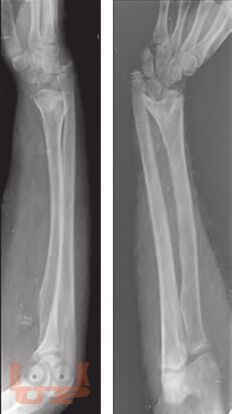

Ортопедические последствия гематогенного остеомиелита верхних конечностей у детей

Авторами представлен многолетний опыт лечения детей с ортопедическими последствиями гематогенного остеомиелита верхних конечностей. На основании комплексного обследования пациентов предложены оптимальные способы лечения детей с данной патологией.

Издание предназначено для травматологов-ортопедов и хирургов широкого профиля.